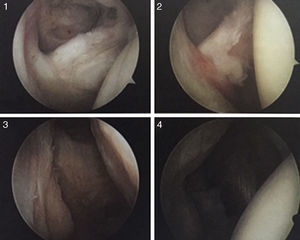

Clasificación por la forma de la lesiónLa clasificación de Ellman y Gartsman (1993) es una de las más usadas por la descripción anatómica de la lesión, lo cual permite realizar un adecuado planteamiento preoperatorio (tabla 4 y figs. 1 y 2).

Clasificación de acuerdo con la calidad del tendónLa calidad del tendón se puede evaluar por TC o RM y su función principal es determinar si el tendón, por su calidad, es reparable. La clasificación más usada es la clasificación de Goutallier (tabla 5), basada en la existencia de infiltración grasa en imágenes de TC. Fuchs ha publicado también una clasificación similar con el uso de RM (figs. 3–6).